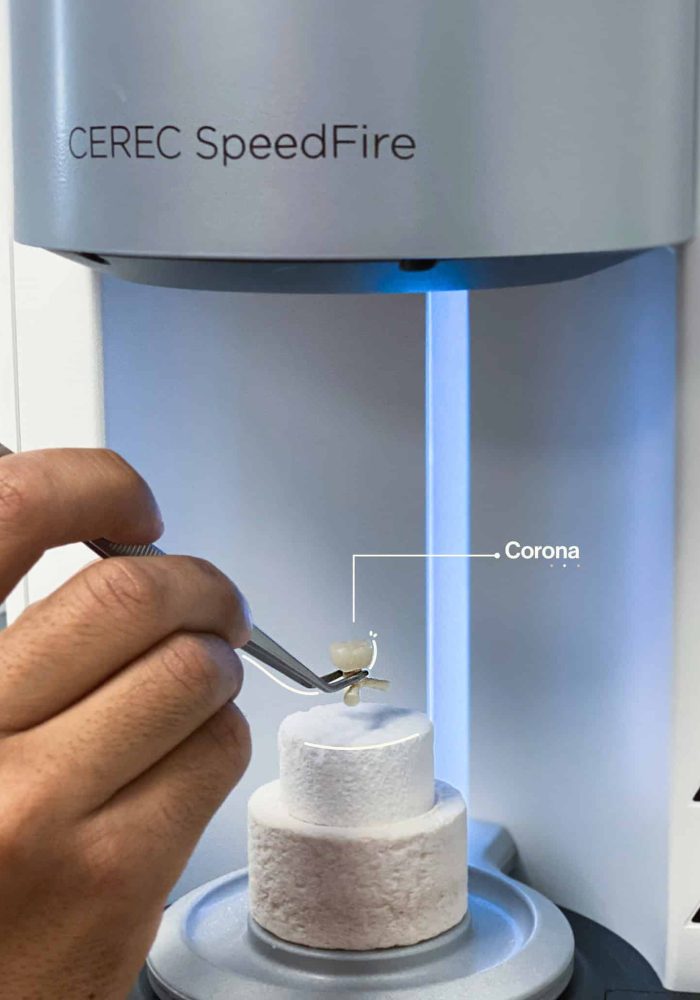

Aesthetic DentistryAesthetic Dentistry

Dental RehabilitationDental Rehabilitation

Restorative DentistryRestorative Dentistry